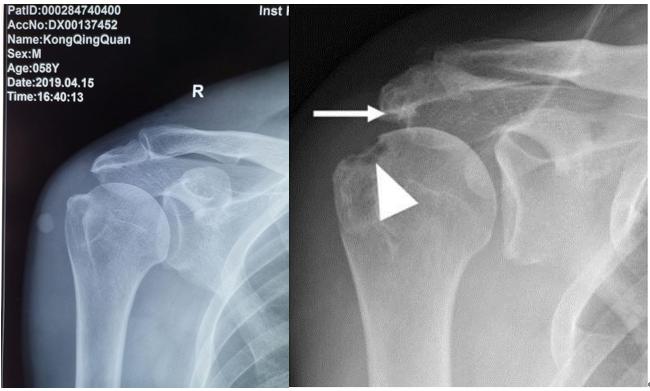

诊断展示:罗教授讲解肩关节X线片